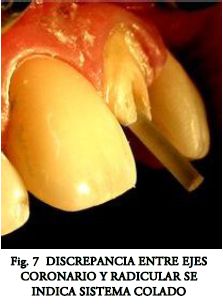

Actualmente existe una abrumadora presencia de trabajos que avalan su uso (7, 8, 12, 13, 14). Sin embargo en nuestro país no han desplazado de forma automática a las técnicas tradicionales. Quizás porque nuestra escuela restauradora clásica (15), basada en aleaciones coladas nobles (y conservadora al máximo de los tejidos dentarios) (Fig.7 a 10), ha obtenido un éxito predecible a lo largo de los años. Pero sus altos costos, compleja manipulación, su casi imposibilidad de remoción para retratamiento, sumado a la aparición de fracturas graves cuando falla la técnica, abren paso a nuevas alternativas que se están adoptando con la debida prudencia.

- Fabricación del Muñón Coronario.- Esta etapa tan fácilmente resuelta por los colados, siempre es problemática en los prefabricados. En casos de discrepancia entre los ejes coronario y radicular (Fig.7) puede ser necesario cambiar de sistema (Figs. 8, 9, 10).